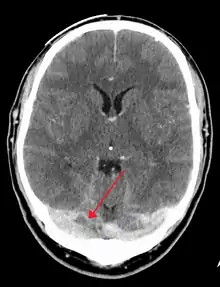

A dural venous sinus thrombosis of the transverse sinus. Greater on the right than left.

There are various neuroimaging investigations that may detect cerebral sinus thrombosis. Cerebral edema and venous infarction may be apparent on any modality, but for the detection of the thrombus itself, the most commonly used tests are computed tomography (CT) and magnetic resonance imaging (MRI), both using various types of radiocontrast to perform a venogram and visualise the veins around the brain.[3]